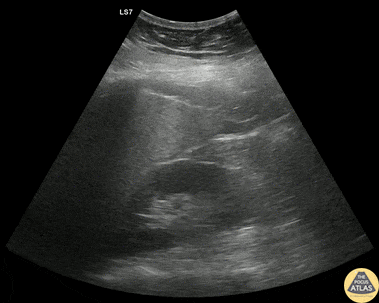

Trauma - Subtle RUQ +FAST

30s F presented with worsening abdominal pain in the setting of a known ectopic pregnancy. FAST exam was very subtly positive in the RUQ, with more free fluid seen in the pelvic/suprapubic view. This clip shows the RUQ view, and a trace amount of free fluid is seen at the liver tip, highlighting the importance of complete visualization of this area when viewing the RUQ. This patient remained hemodynamically stable, and so was managed expectantly rather than with surgical exploration. Dr. Lindsay Howe, PGY-3 Denver Health Residency in Emergency Medicine